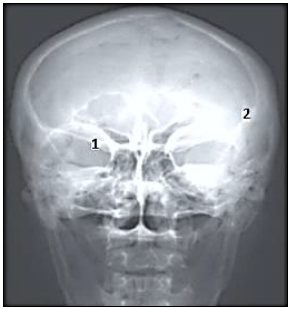

Com base na imagem radiológica apresentada, os números expostos referem-se, respectivamente, a quais estruturas anatômicas?

Com base na imagem radiológica, os números nela demonstrados representam, respectivamente, as seguintes estruturas anatômicas: